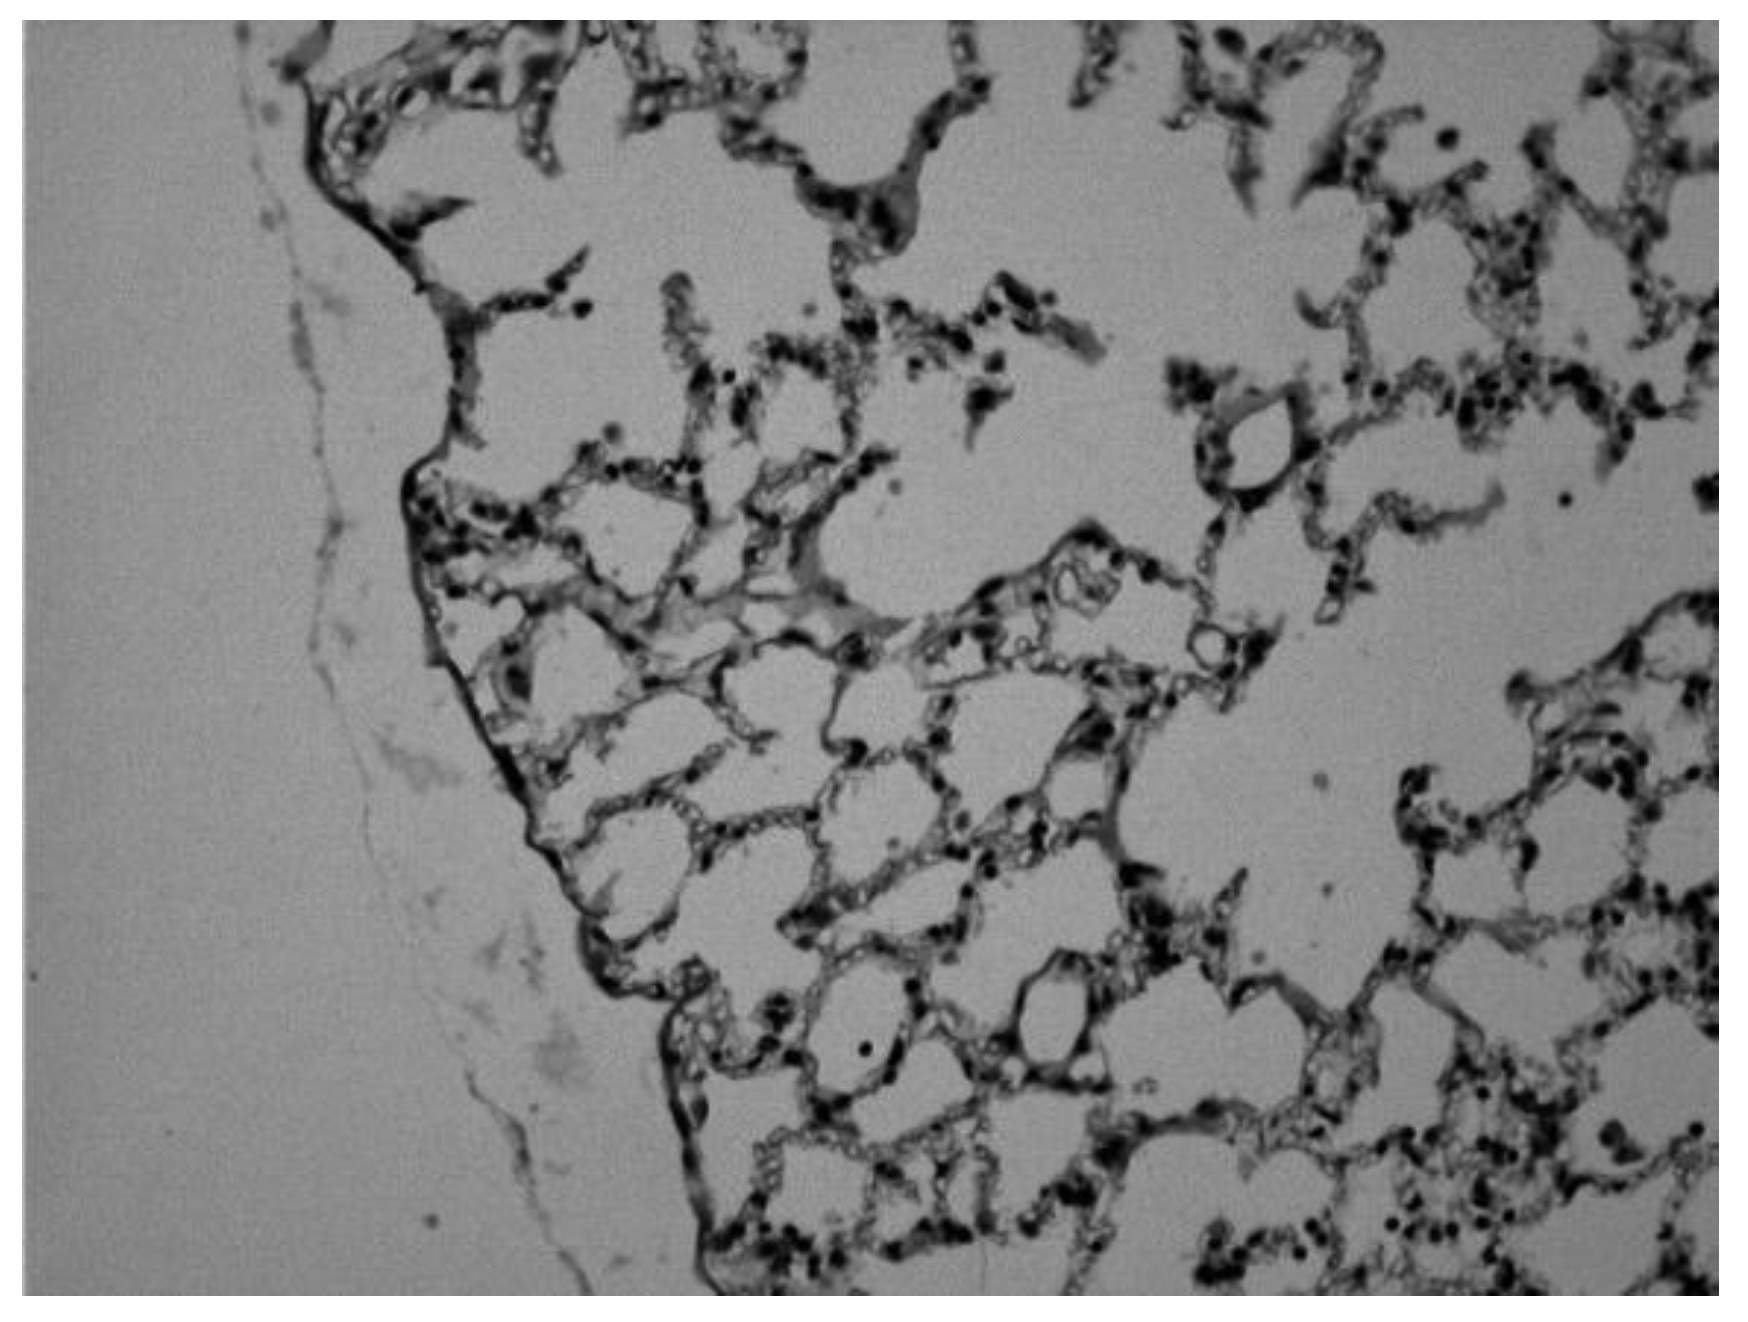

Histological changes observed in the lung of mouse sensitized with ovalbumin and treated with theophylline in oral and intravenous solution.

Image 1. Lung of a control animal in which we can observe normal alveolar spaces (Hematoxylin-eosin 20x).